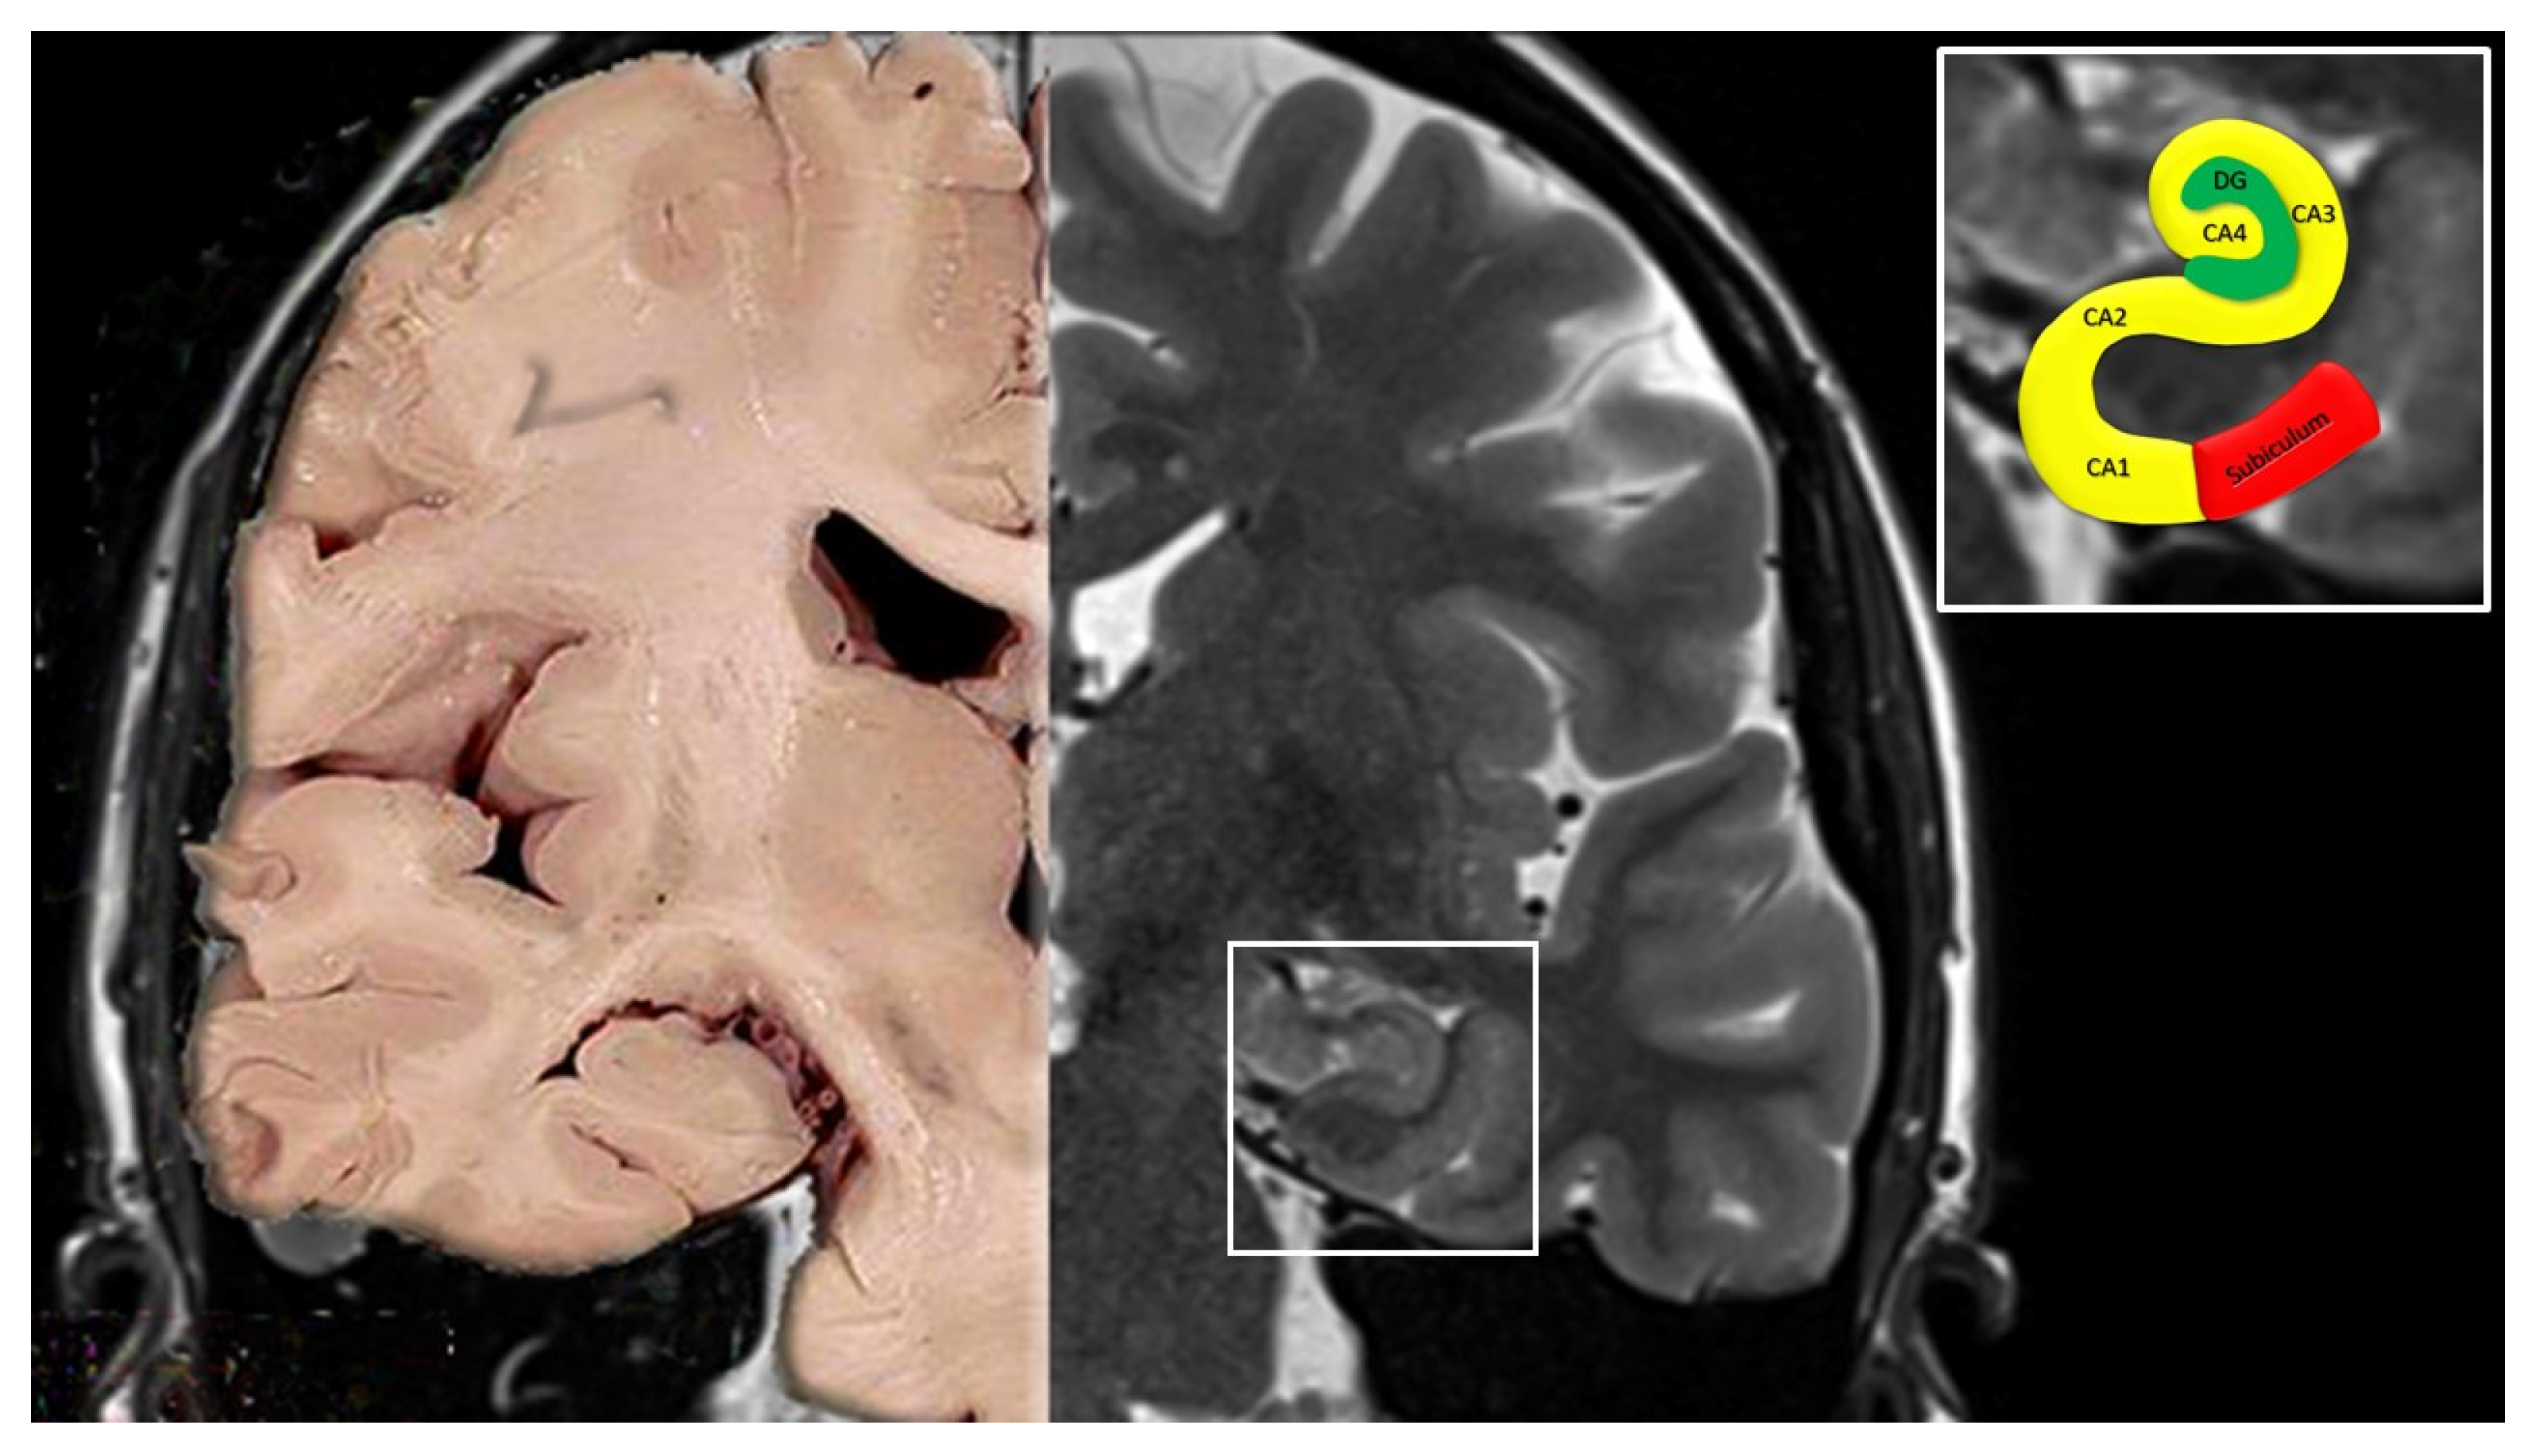

2. Anatomy of the Hippocampus

- Cornu ammonis (Hippocampus Proper)

- CA1 continues from the subiculum. Pyramidal somata are triangular, small and scattered.

- CA2 is composed of large, ovoid, densely packed somata, making the stratum piramidale dense and narrow, in sharp contrast to CA1.

- CA3 corresponds to the curve, or genu, of the cornu ammonis. Pyramidal somata are like those in CA2, but less numerous. A typical feature of this field is the presence of the mossy fibers, i.e., unmyelinated fibers arising from the gyrus dentatus.

- Dentate gyrus

- Large Ventral Intrahippocampal Arteries vascularize CA1 and CA2.

- Large Dorsal Intrahippocampal Arteries supply CA3 and sometimes CA2, as well as CA4 and the distal part of the dentate gyrus.

- Small Ventral Intrahippocampal Arteries vascularize the proximal part of the gyrus dentatus.

- Small Dorsal Intrahippocampal Arteries have a small intrahippocampal territory limited to CA3 and the adjacent part of CA4 [15].

- MRI studies showing in patients with TGA DWI changes in the hippocampal CA1 neuronal field, a region involved in the process of memory consolidation, provide support for the arterial ischemia hypothesis [3,4]. However, these changes are inconsistently present, reversible with time, and do not respect a clear arterial territory [3] (see Part II of this review for details). Furthermore, lesions associated with TGA are generally seen 24–72 h after symptom onset and disappear soon after; instead, symptoms of a clear ischemic nature are commonly associated with permanent lesions on MRI [3,4,44,45]. Finally, no abnormalities have been found in intracranial magnetic resonance angiography and in perfusion-weighted imaging during acute episodes, thus making the hypothesis of an arterial ischemia less likely [13,14,46,47].

- The intrahippocampal territories of the deep blood arterial vessels show frequent variations, therefore, in most cases, CA1 is only vascularized by the large ventral intrahippocampal arteries, whereas CA2 and CA4 fields and the gyrus dentatus are vascularized by different arterial groups [74];